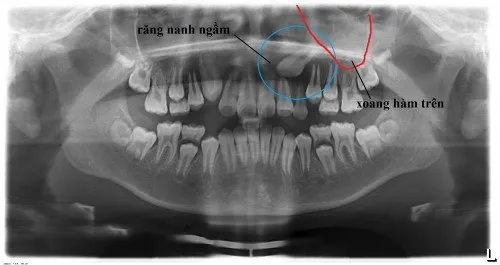

- Mọc ngầm hoàn toàn: Răng nằm hoàn toàn bên dưới nướu và trong xương hàm. Đây là trường hợp khó phát hiện nhất nếu không chụp X-quang.

- Răng Nanh (Răng số 3): Răng nanh có vai trò thẩm mỹ và chức năng cắn xé rất quan trọng. Đây là răng thường mọc ngầm thứ hai sau răng khôn. Nếu răng nanh bị ngầm, nó có thể gây mất thẩm mỹ nghiêm trọng (thiếu răng) và ảnh hưởng đến toàn bộ cấu trúc khớp cắn.